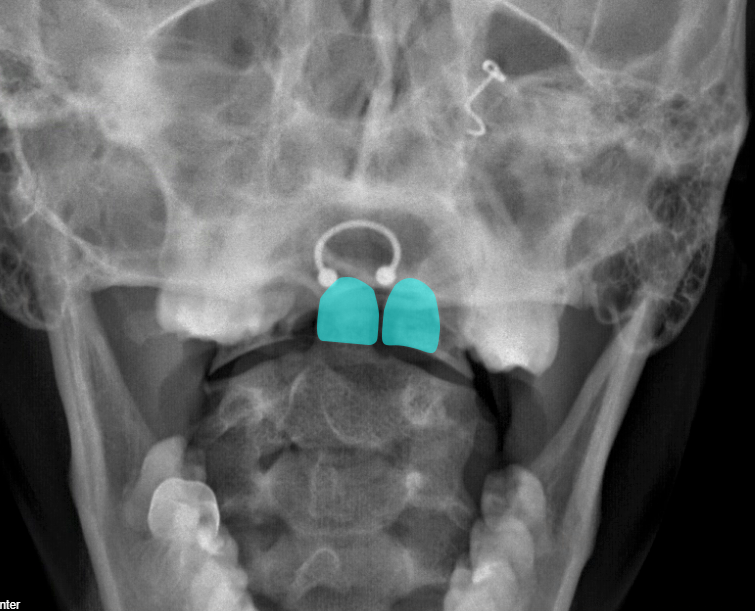

I’ll highlight two structures. Do you see it now?

The line was an overlap of one of the incisors – a so-called “tooth artifact”.

For the open mouth view in a cervical spine series to be “adequate,” we need to see the entire dens and the lateral masses of C1 as they articulate with C2. In this case, we can’t really see the entire dens and what we can see is obscured by teeth. We can see the most inferior bit of the lateral masses, enough to see normal alignment, but we can’t really see any of the body of C1.

Either this patient didn’t open their mouth wide enough, or the image wasn’t shot at a steep enough angle to get the teeth out of the way.